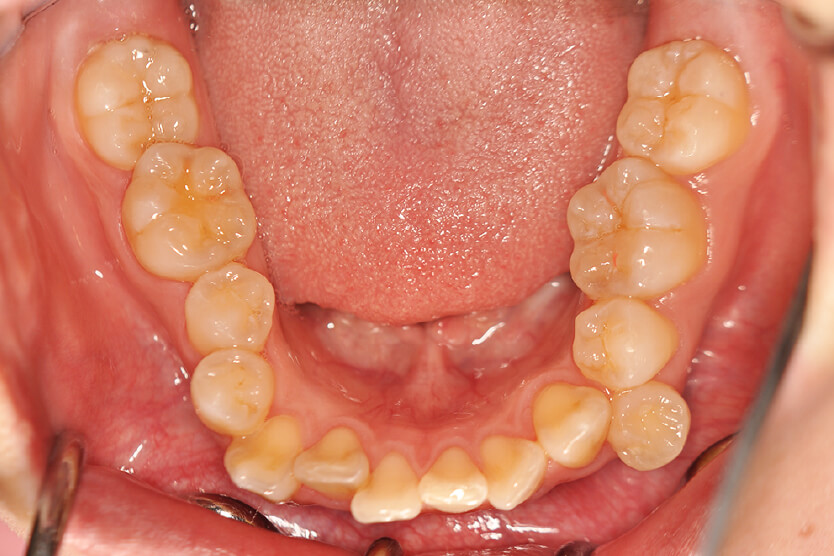

| 治療内容の詳細 | 初診時21歳の女性で、八重歯、歯のがたつき主訴として来院されました。 検査の結果、上下顎前歯部叢生を伴うアングルⅡ級1類不正咬合と診断しました。 治療としては、上下顎左右第一小臼歯を抜歯し、セルフライゲーションブラケット装置(デーモンシステム)とマウスピース矯正装置(インビザライン)で歯の配列を行いました。 治療期間は、1年4か月でした。 |